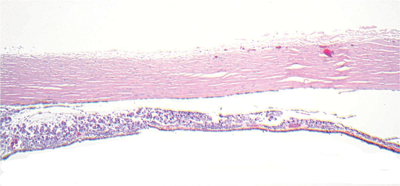

Figure 1 - sclera and choroid

Figure 1.

1. What does Figure 1 show?

1. This shows an abnormal infiltrate of cells in the choroid. Normal choroid is seen on the far right.